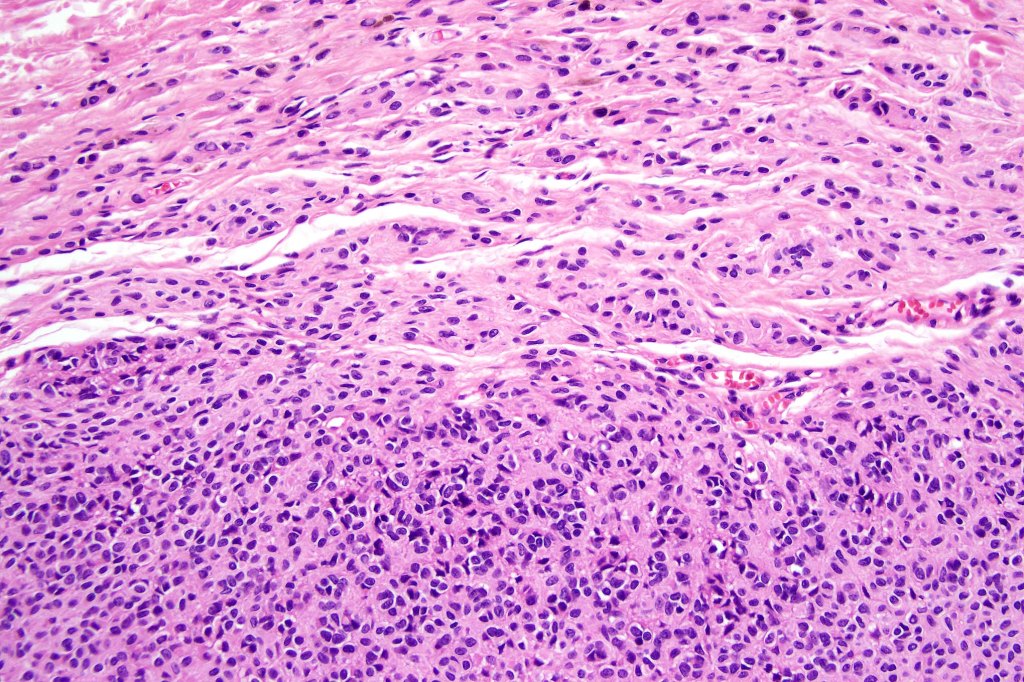

•The nodule generally merges with the adjacent nevus but sometimes it can be sharply circumscribed

•It is hypercellular and most often composed of epithelioid cells showing little pleomorphism & only occasional mitoses

•Nuleoli are small

•The constituent cells are generally larger than the adjacent nevus cells

•Some examples show more marked pleomorphism with prominent nucleoli and increased mitotic activity but abnormal mitoses are not a feature. These are not associated with any sinister biological potential

•Absence of necrosis, hemorrhage or Pagetoid spread in the overlying epidermis

•Spindle cell, small blue cell, blue nevus-like features, Spitzoid & proliferative nodules with mesenchymal differentiation (myofibroblastic, chondroid & osteoid) can be seen